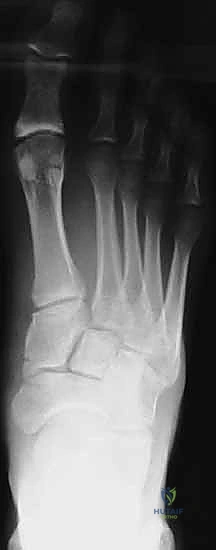

2. التصوير بالأشعة السينية (X-Rays) مع تحميل الوزن

الأشعة السينية العادية قد لا تظهر الإصابة إذا لم تكن العظام مزاحة بشكل كبير. السر يكمن في طلب أشعة سينية أثناء وقوف المريض وتحميل وزنه على القدم المصابة (Weight-bearing X-rays).

* يبحث الدكتور هطيف عن "علامة الفليك" (Fleck Sign)، وهي قطعة عظمية صغيرة مكسورة ومسحوبة من قاعدة المشط الثاني أو العظم المسماري الإنسي، وهي دليل قاطع على تمزق رباط ليزفرانك.

* كما يتم قياس المسافة بين قاعدة المشط الأول والمشط الثاني. أي اتساع يزيد عن 2 ملم يُعتبر غير طبيعي ويشير إلى عدم الاستقرار.